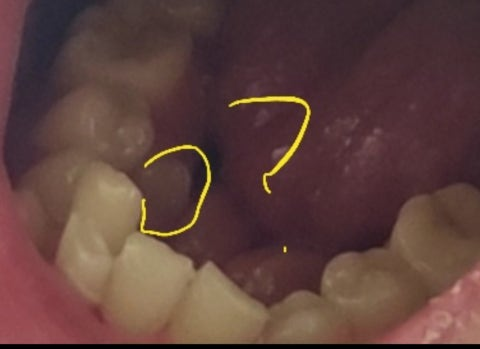

최근까지 안 나온 이가 거울을보니 나와있네요~~ 빼면되는것인지???

무슨 이유로 나는건가요? 20중반이에요

혀로 움직이면 뭔가 있는 느낌만 들고

불편하지는 않지만 병원가면 발치하나요~~????

영구치하가 맹출된 시기에 맹추 순서가 잘못된다면. 치아가 맹출된 공간이 없어지기 때문에 안쪽에서 뻐드렁니로 날 수가 있습니다 이런 경우에는 치아 사이에 충치나. 치주질환을 유발할 수 있기 때문에 발치를 하는 것이 일반적입니다 자세한 확인을 위해서 치과에서 진료를 받아 보세요

치열이 많이 삐뚤어 관리가 힘들어 보이며 해당 치아까지 포함하여 교정치료가 필요해보입니다.

과잉치라면 발치를 하시는게좋을것같습니다. 관리가 안되면 다른 치아까지 충치가 생길수도 있습니다